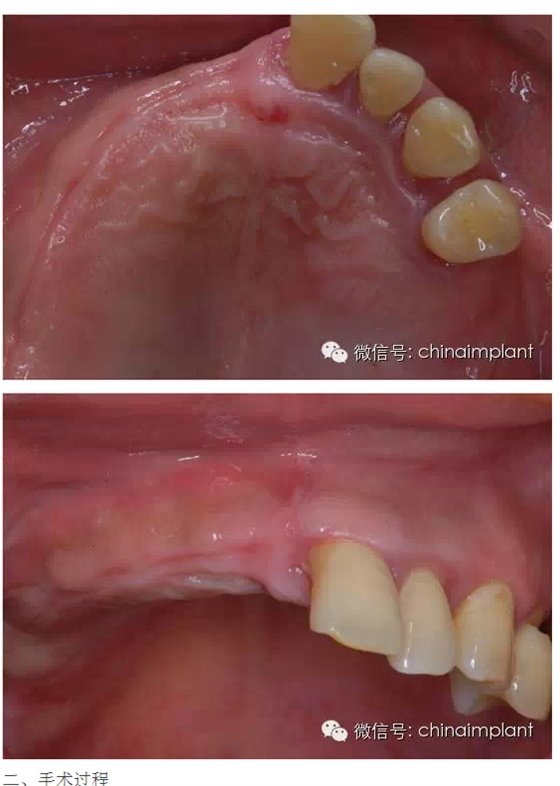

本案例已經(jīng)將近10年了(2005年12月),但是修復(fù)效果個(gè)人認(rèn)為很不錯(cuò),所以拿出來和大家分享。